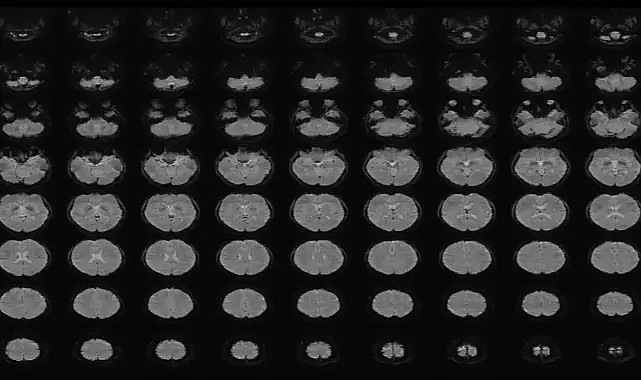

Araştırmada 22–37 yaş aralığında altı kişinin beyin aktivitesi, sesiz kısa videolar izlerken fMRI ile kaydedildi. Katılımcılar toplam 2.180 video izledi; videolarda nesneler, hareketler ve mekânlar yer alıyordu.

Yapay zekâ, önce videoların açıklamalarını sayısal verilere dönüştürdü. Ardından “decoder” adı verilen ayrı modeller, bu sayısal verileri beyin taramalarıyla eşleştirmeyi öğrendi. Böylece sistem, katılımcıların daha önce görmediği videoları izlerken veya hatırlarken oluşan beyin aktivitelerini çözümleyip betimleyici cümleler üretmeye başladı.